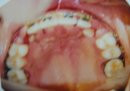

Canine teeth are the sharp, pointy teeth that are located between the incisors and the premolars. An impacted canine means the tooth has only grown partially through the gums and have not yet erupted into the regular position, even after the normal eruption period. The canine tooth is a critical tooth in the dental arch and plays an important role in your “biteâ€. The canine teeth are very strong biting teeth because they have the longest roots of any human teeth. They are designed to be the first teeth that touch when your jaws close together so they guide the rest of the teeth into the proper bite. It is also important for aesthetic reasons as it is a front tooth, and can be seen during talking or smiling.

Impacted canines can result from a genetic factor (means that the child gets this condition from the parents), or an environmental factor (means that the tooth did not erupt due to some obstacles present in its eruption path). Â Also, the canine (especially the upper ones) is the tooth that gets impacted most easily as it has a longest eruption path amongst all teeth. It starts forming somewhere below the eye, and slowly descends and erupts into the mouth. Therefore, in such a long distance, there may be a lot of things that can go wrong for the tooth to erupt.

- overcrowding – which means that the teeth is relatively bigger than the mouth. This leads to inadequate space for the mouth to allow all the normal amount of teeth to erupt in a nicely aligned fashion.

An impacted tooth can grow at an angle toward the other teeth. When this happens, the tip of the tooth pushes toward the root of the next tooth (as it is still embedded inside the gums) , and that tooth is forced to push against another tooth. A domino effect is created that can cause all of the teeth to be crooked.